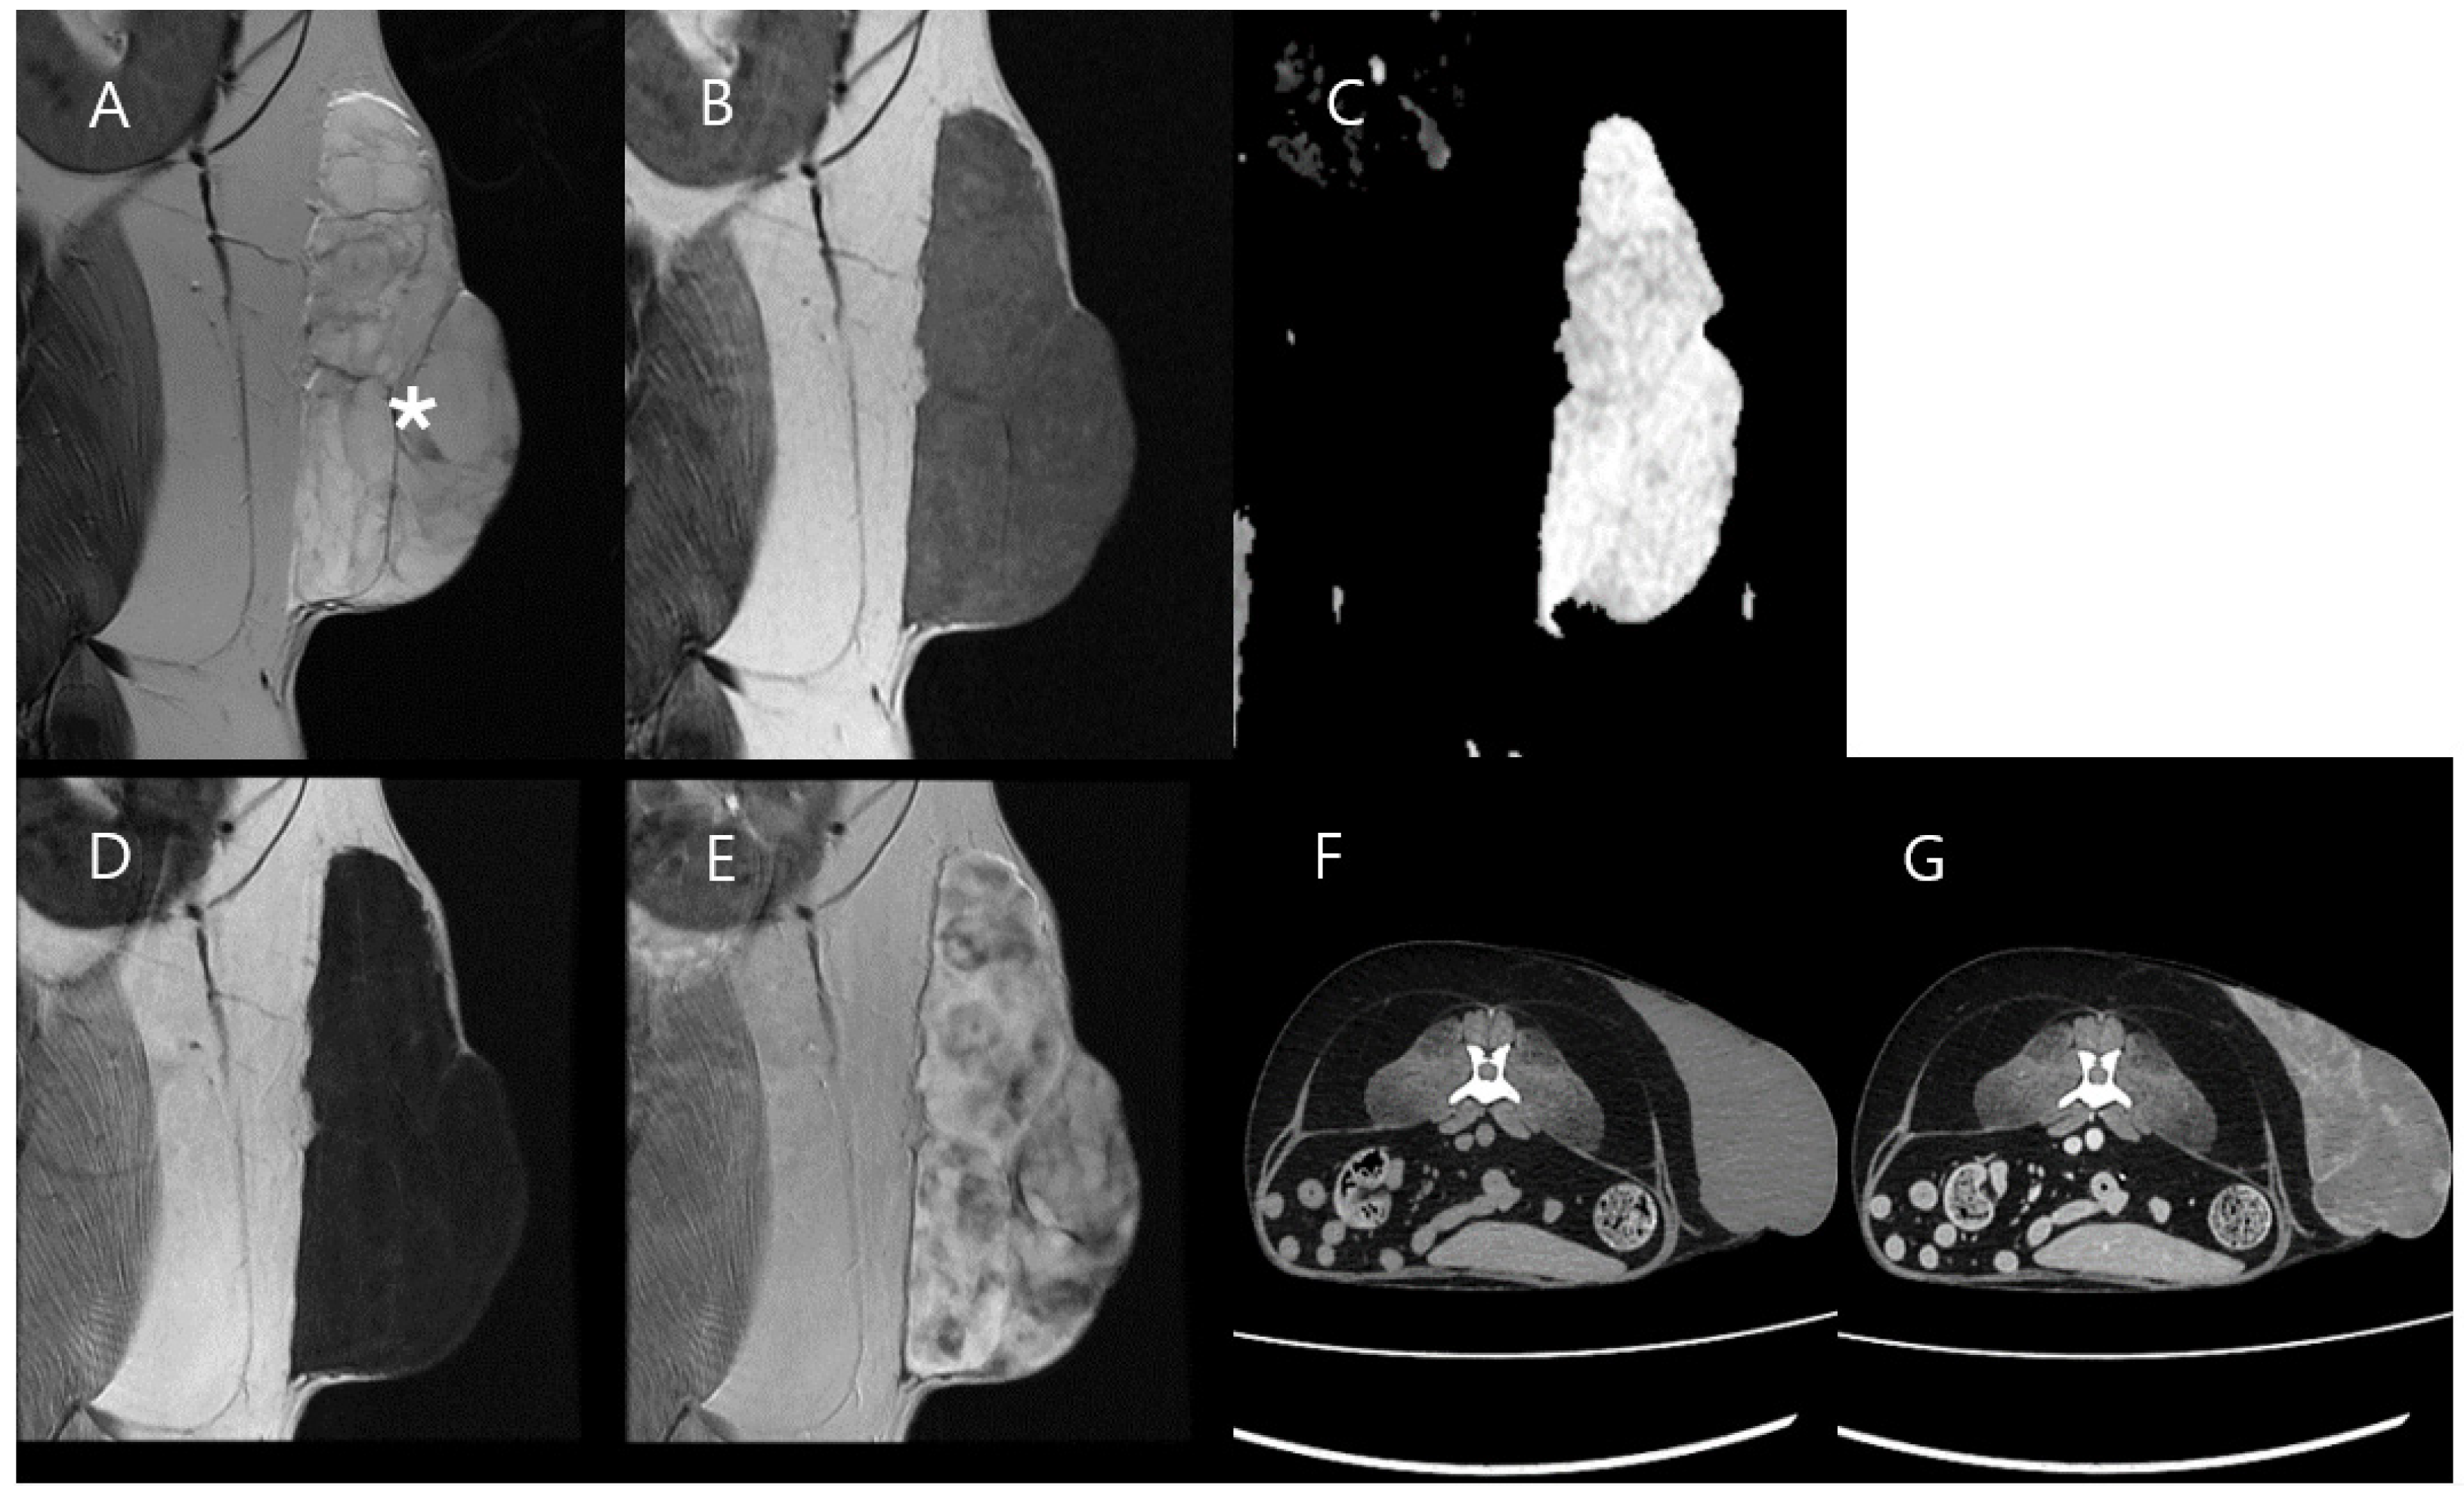

3.2. Case 2

| Mass Type | Soft Tissue Sarcoma (Hemangiopericytoma, Grade II) | Normal Region (Adjacent Muscle) | Soft Tissue Sarcoma (Myxosarcoma, Grade I) | Normal Region (Adjacent Muscle) |

| Ktrans (min−1), mean ± SD | 1.393 ± 0.026 (Peripheral mass region) 0.013 ± 0.079 (Central mass region) | 0.089 ± 0.042 | 0.176 ± 0.064 | 0.059 ± 0.141 |

| kep (min−1) mean ± SD | 5.137 ± 0.643 (Peripheral mass region) 0.992 ± 1.409 (Central mass region) | 0.381 ± 0.118 | 0.305 ± 0.108 | 0.699 ± 0.883 |

| Ve mean ± SD | 0.499 ± 0.107 (Peripheral mass region) 0.014 ± 0.043 (Central mass region) | 0.239 ± 0.089 | 0.585 ± 0.209 | 0.088 ± 0.115 |

| Vp mean ± SD | 0.241 ± 0.099 (Peripheral mass region) 0.011 ± 0.00006 (Central mass region) | 0.001 ± 0.00006 | 0.003 ± 0.00006 | 0.019 ± 0.045 |

| TIC Type | Fast wash-in, Fast wash-out (Peripheral mass region) Plateau (Central mass region) | Progressive | Progressive | Plateau |